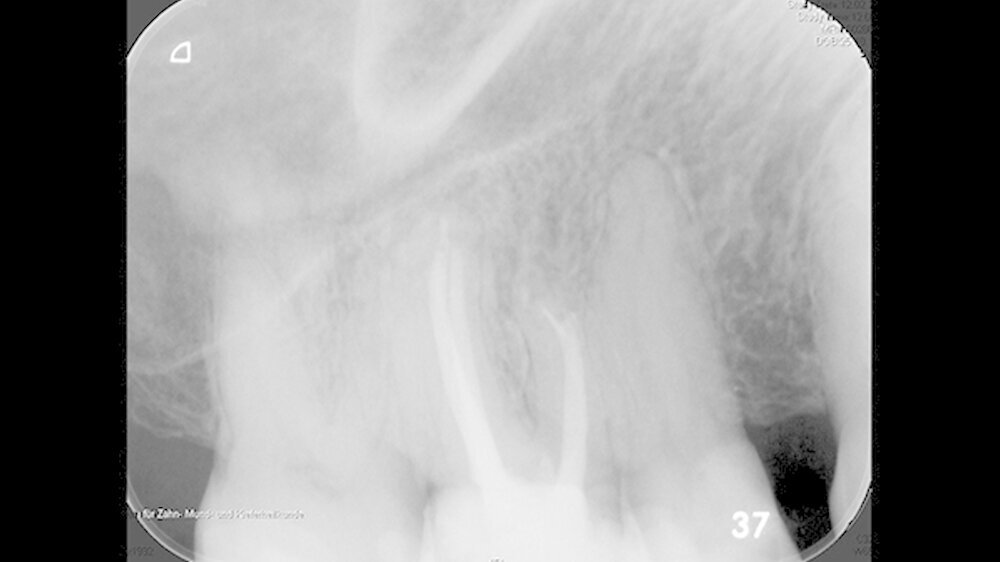

Mit einem ultraschallgetriebenen diamantierten, abgewinkelten Instrument wurden beide Wurzelkanäle der mesiobukkalen Wurzel von retrograd präpariert (Abbildung 3). Das frakturierte Instrument konnte so dargestellt (Abbildung 4) und entfernt werden.